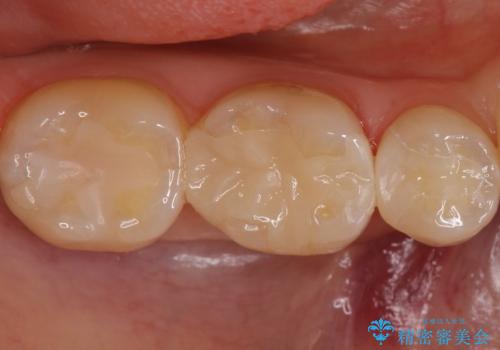

歯と歯の間の虫歯 セラミックインレーでの治療

- 矯正後の検査で歯と歯の間の虫歯が確認された患者様です。

虫歯の除去後、セラミックインレーで修復していきます。

- 右下5 セラミックインレー 77,000円費用は治療当時の料金となります

レントゲン画像からは読み取りづらいですが、視診にて歯の一部が黒く透けているのが確認できました。

小さな虫歯でも見落とさずに精度の良い修復をすることで二次う蝕のリスクを減らすことができます。